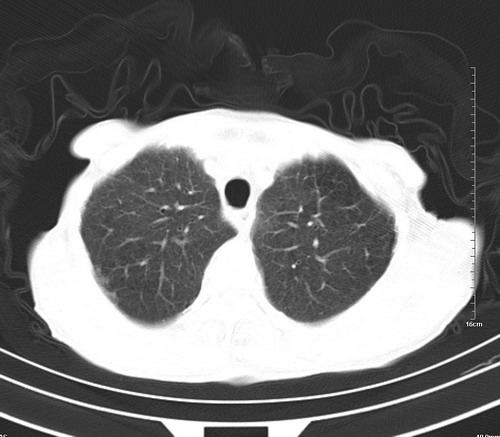

中后纵隔占位,气管、食道受压、变形、移位。恶性可能性大。

1 气管旁、隆突下淋巴结明显肿大,肝左叶外侧段低密影,都考虑转移。

纵隔淋巴结肿大,考虑转移而来

肺癌,纵隔淋巴结转移,肝左叶病变考虑为转移病灶。

后中纵隔团块影,伴气管、食道受压移位,首先考虑转移瘤,肝s5段低密度灶。建议增强检查,另外其结肠是否有问题请提供,右肺部分肺叶局限含气增多,考虑局限肺气肿。

建议强化检查,考虑纵隔型肺癌,小细胞可能性大。

后中纵隔淋巴结肿大,首先考虑转移瘤。